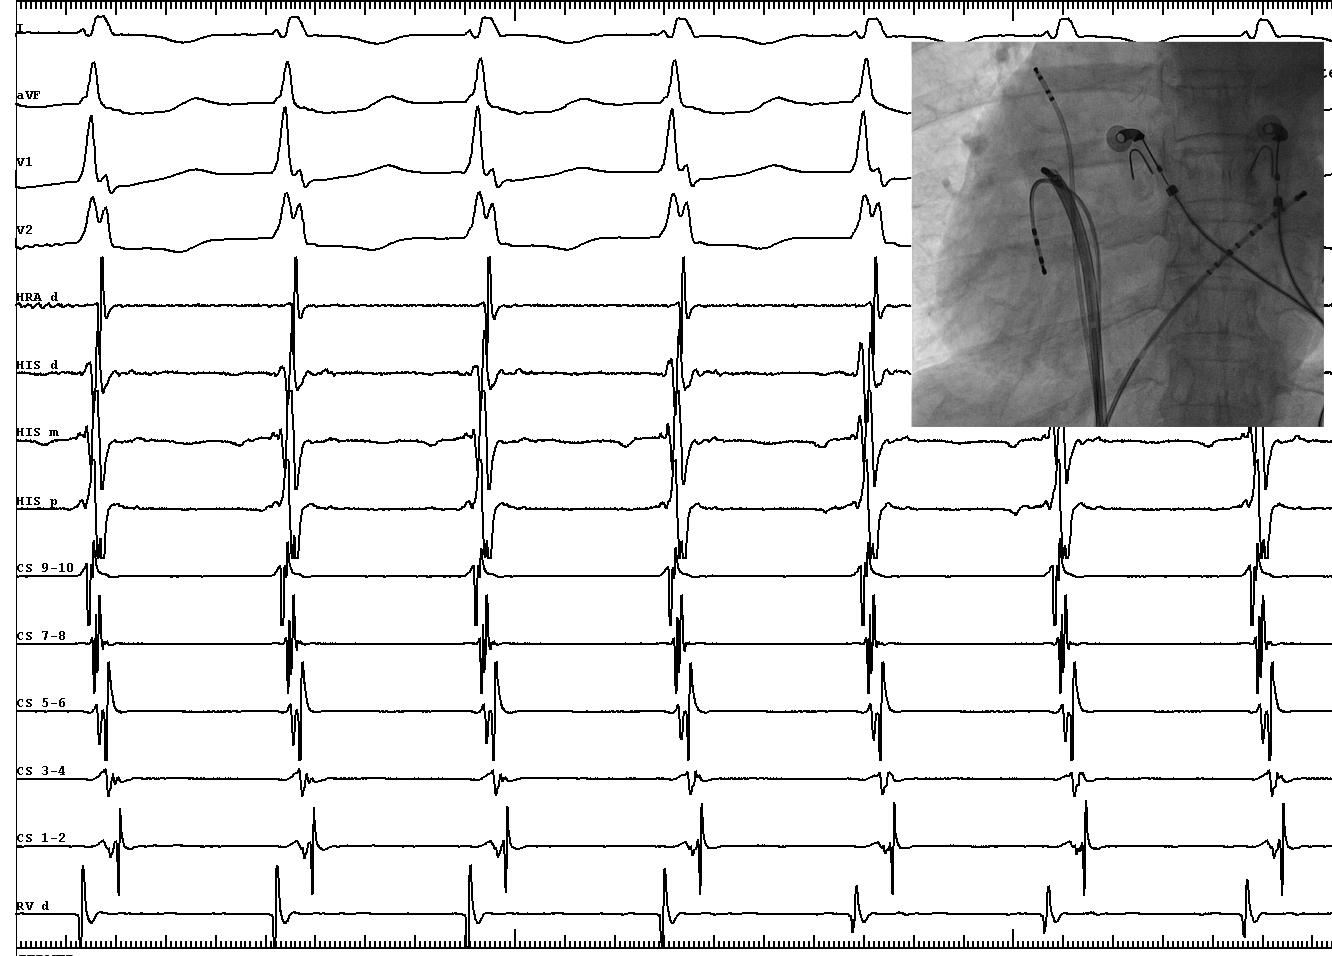

EP study - Sinus rhythm

sinus_post_HIS.jpg